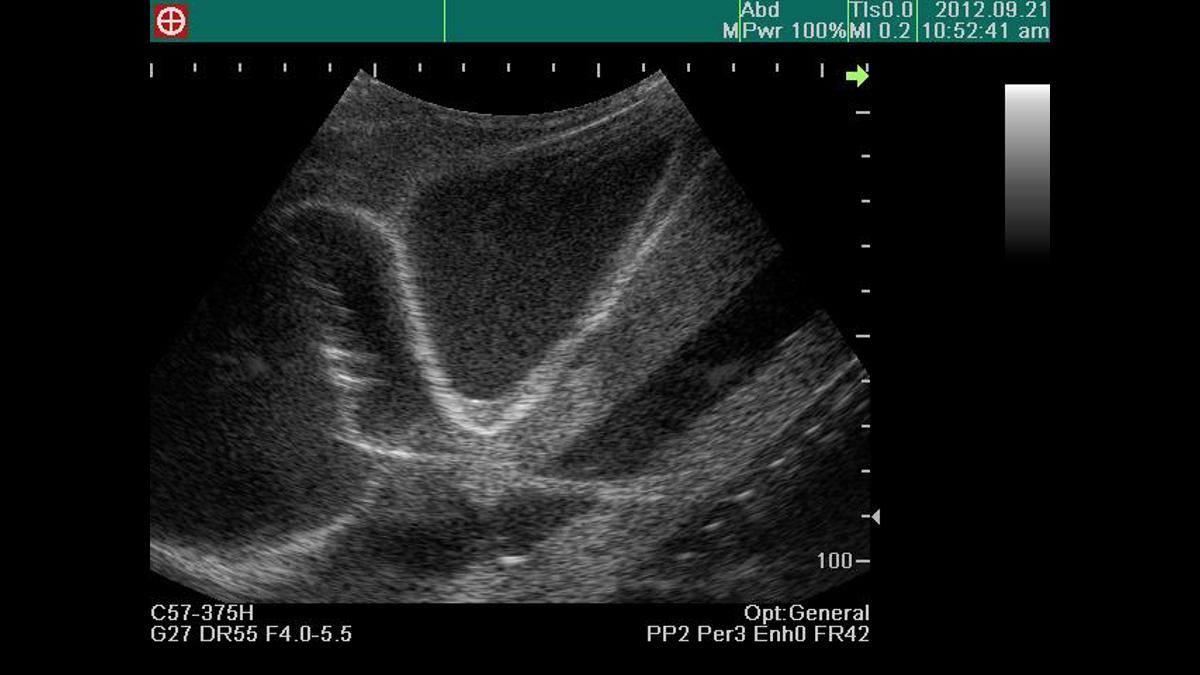

This ultrasound compatible model is a multifaceted trainer that facilitates training in thoracentesis and pericardiocentesis. The combined model allows trainees to use the clear ultrasound image provided to accurately perform both procedures.

The ability to pierce the pericardial sac using ultrasound guidance provides learners with the platform to repeatedly practice patient safety during the pericardiocentesis procedure.

Confirmation of ventricles, ribs, pericardium, liver and main artery under ultrasound scanning

Visualization of pericardial fluid using ultrasound scanning